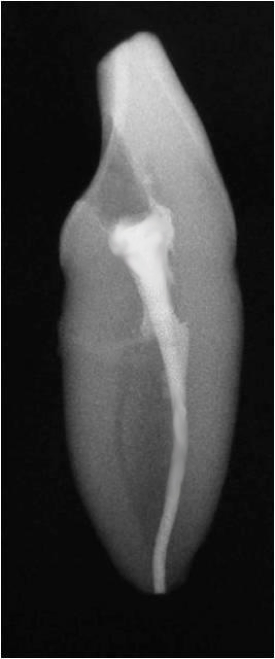

Fig 22. Internal resorption.

Figure 22

Another time when a post cannot be placed is when there is internal or external resorption. In the case shown in Figure 22, internal resorption occurred. Today it would be much easier to ascertain with CBCT. Here, the clinician filled the resorption with gutta-percha, and then above the gutta-percha, the mid-root coronal section was filled with composite. Because of how weakened the tooth was already, the clinician wanted to do whatever was possible to prevent it from weakening further. Figure 23 shows the postoperative radiograph, and Figure 24 shows the 2-year checkup. The only post that could be placed would have been a fiber post.